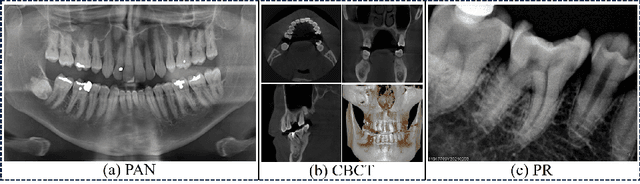

Abstract:Efficient analysis and processing of dental images are crucial for dentists to achieve accurate diagnosis and optimal treatment planning. However, dental imaging inherently poses several challenges, such as low contrast, metallic artifacts, and variations in projection angles. Combined with the subjectivity arising from differences in clinicians' expertise, manual interpretation often proves time-consuming and prone to inconsistency. Artificial intelligence (AI)-based automated dental image analysis (DIA) offers a promising solution to these issues and has become an integral part of computer-aided dental diagnosis and treatment. Among various AI technologies, deep learning (DL) stands out as the most widely applied and influential approach due to its superior feature extraction and representation capabilities. To comprehensively summarize recent progress in this field, we focus on the two fundamental aspects of DL research-datasets and models. In this paper, we systematically review 260 studies on DL applications in DIA, including 49 papers on publicly available dental datasets and 211 papers on DL-based algorithms. We first introduce the basic concepts of dental imaging and summarize the characteristics and acquisition methods of existing datasets. Then, we present the foundational techniques of DL and categorize relevant models and algorithms according to different DIA tasks, analyzing their network architectures, optimization strategies, training methods, and performance. Furthermore, we summarize commonly used training and evaluation metrics in the DIA domain. Finally, we discuss the current challenges of existing research and outline potential future directions. We hope that this work provides a valuable and systematic reference for researchers in this field. All supplementary materials and detailed comparison tables will be made publicly available on GitHub.

Abstract:Deep learning (DL), a pivotal technology in artificial intelligence, has recently gained substantial traction in the domain of dental auxiliary diagnosis. However, its application has predominantly been confined to imaging modalities such as panoramic radiographs and Cone Beam Computed Tomography, with limited focus on auxiliary analysis specifically targeting Periapical Radiographs (PR). PR are the most extensively utilized imaging modality in endodontics and periodontics due to their capability to capture detailed local lesions at a low cost. Nevertheless, challenges such as resolution limitations and artifacts complicate the annotation and recognition of PR, leading to a scarcity of publicly available, large-scale, high-quality PR analysis datasets. This scarcity has somewhat impeded the advancement of DL applications in PR analysis. In this paper, we present PRAD-10K, a dataset for PR analysis. PRAD-10K comprises 10,000 clinical periapical radiograph images, with pixel-level annotations provided by professional dentists for nine distinct anatomical structures, lesions, and artificial restorations or medical devices, We also include classification labels for images with typical conditions or lesions. Furthermore, we introduce a DL network named PRNet to establish benchmarks for PR segmentation tasks. Experimental results demonstrate that PRNet surpasses previous state-of-the-art medical image segmentation models on the PRAD-10K dataset. The codes and dataset will be made publicly available.